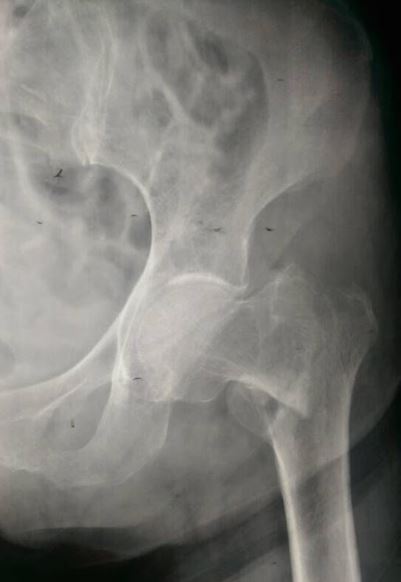

Intertrochanteric Fractures are extracapsular hip fractures in which the fracture line extends between greater and the lesser trochanters.

Waxaa caadiyan Jabkan loo kala saaraa Stable iyo Unstable pattern iyadoo stable fractures ka lagu manage gareeyo Sliding Hip Screw ama loo yaqaan Dynamic Hip Screw (DHS) halka Unstable fractures kana lagu xaliyo Intramedullary Nail (IMN).